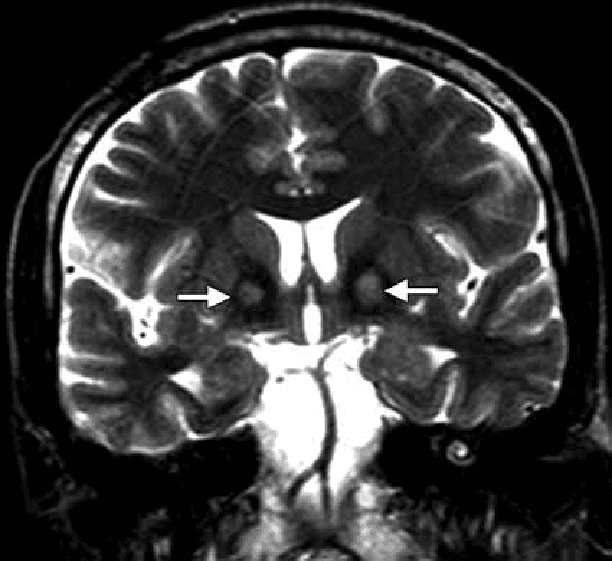

متلازمة هالرفوردن سباتز: الأسباب والأعراض والتشخيص والعلاج